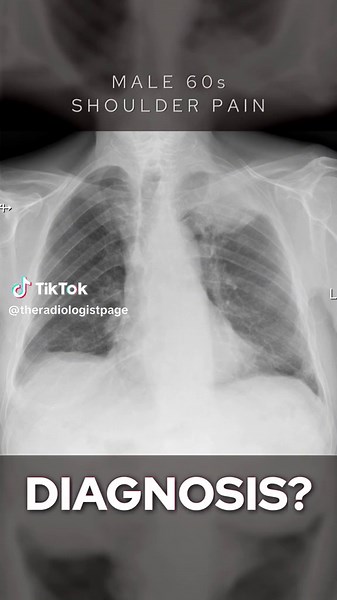

Views - Chest X-Ray

X-ray - Shoulder X-ray

X-Ray - Shoulder